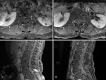

Stem cell therapy can present clinicians with challenging clinical scenarios, as access to such treatments outpaces the research into their efficacy and safety due to the burgeoning trend of international travel to acquire stem cell therapy, or "stem cell tourism." Treatment of neurologic conditions remains an enticing potential application of stem cell therapy, often administered intrathecally. In response to such therapy, multiple adverse events have been described in the literature, including neoplasms, demyelinating disease, and seizures, among others. We present a case of symptomatic inflammatory cauda equina nerve root hypertrophy due to intrathecal stem cell infusion, representing a rare but significant complication.